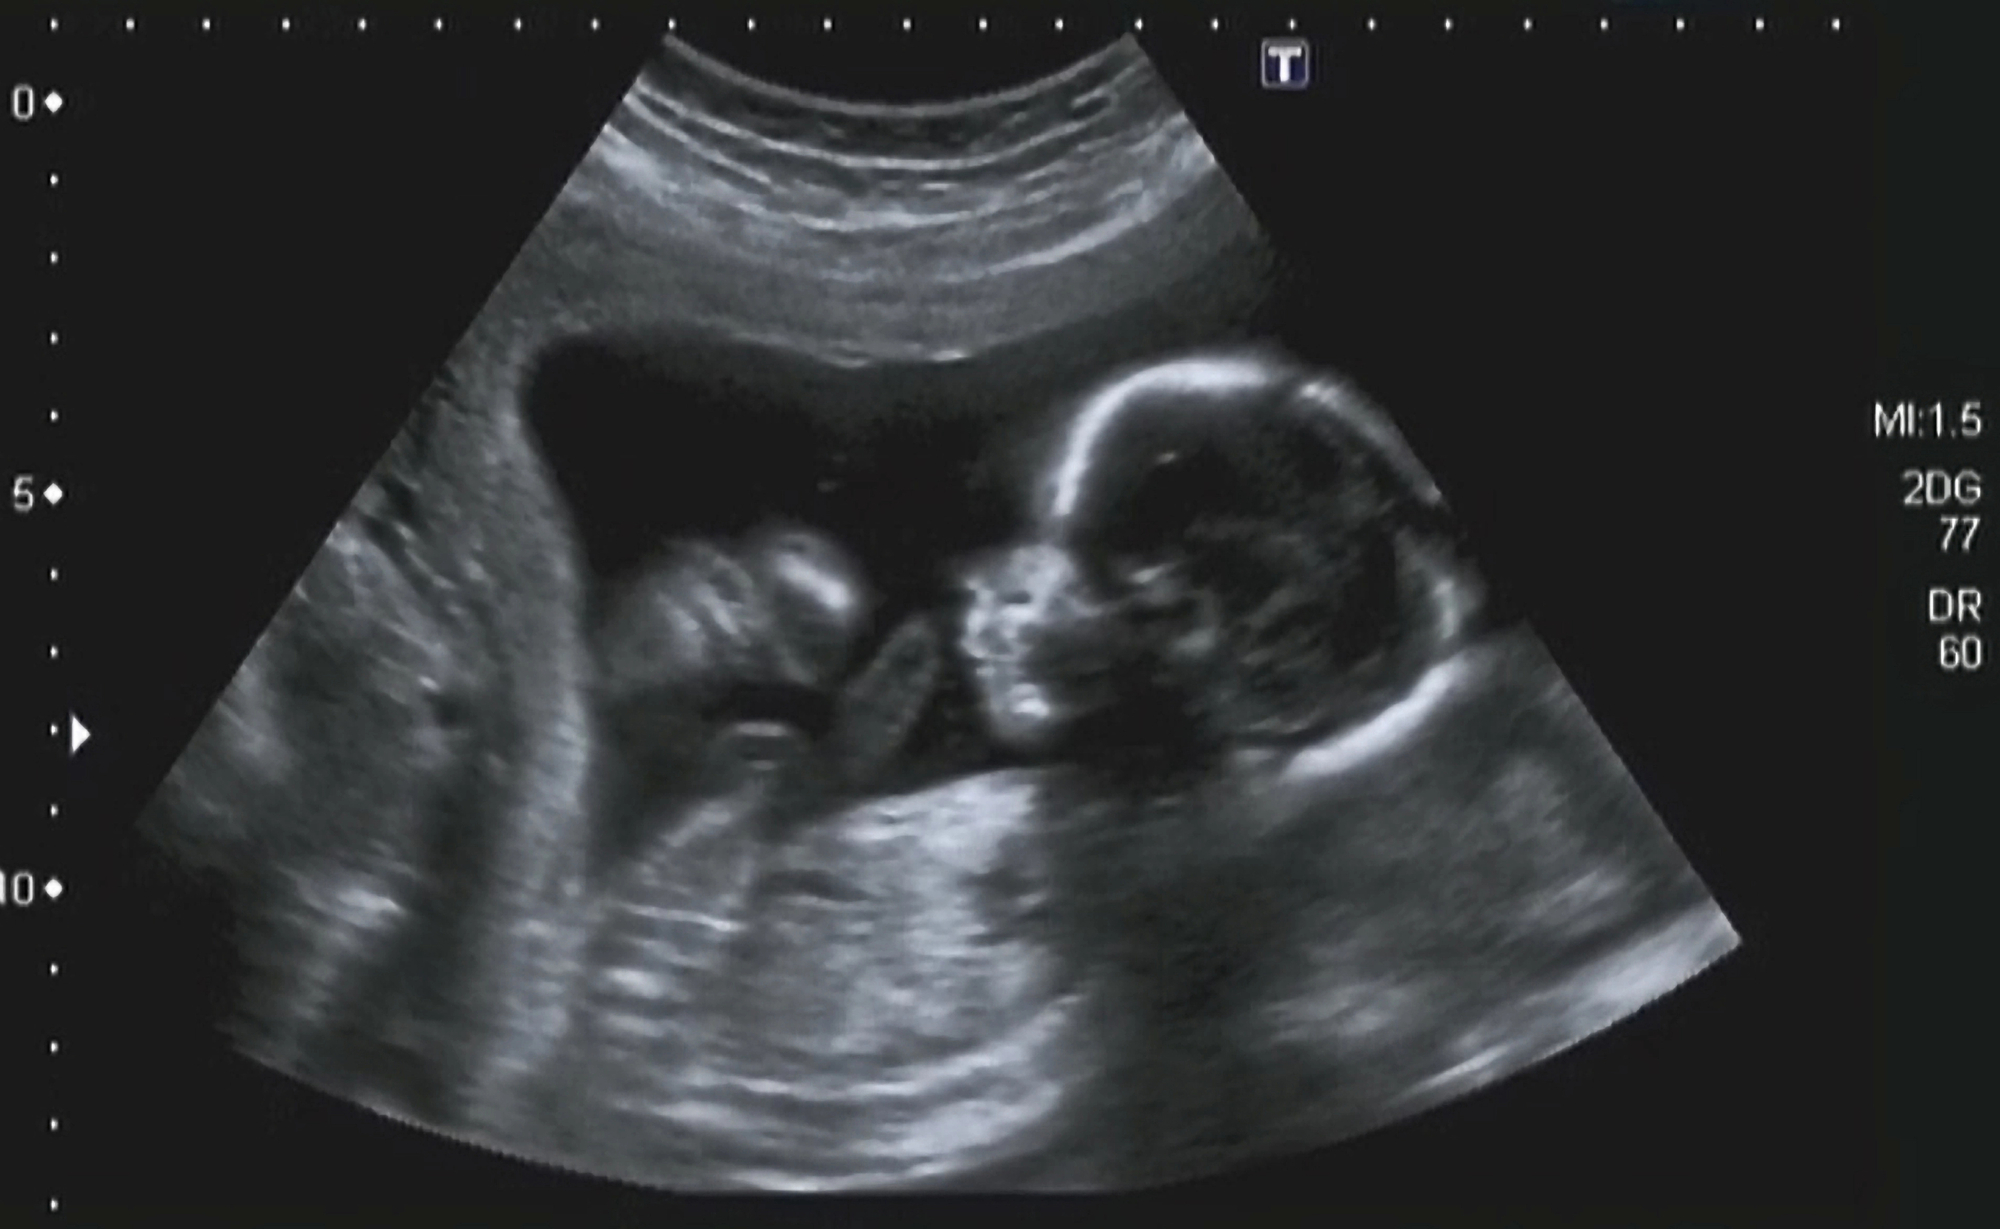

Na prethodnom UZV prije 3 tjedna u ambulanti su mi rekli da mjere odgovaraju, da bi danas rekli da je glavica za 34+3 , te trbuh za 35+4, femur 68. A TT ista ko i prošli put 2790 otprilike. Plodova voda je gušća . PI 0.99, RI 0.63. pokreti uredni. Brine me jer doktor nije rekao ništa, a tu je razlika i po 4 tjedna u razvoju, te kilaza nije narasla ništa. Takodjer, ne znam ni šta bi značilo to da je plodna voda gusta. Trebam li drugo mišljenje ? Ili se ne trebam brinuti, sljedeći pregled će biti u 40tom tjednu, za 8 dana.